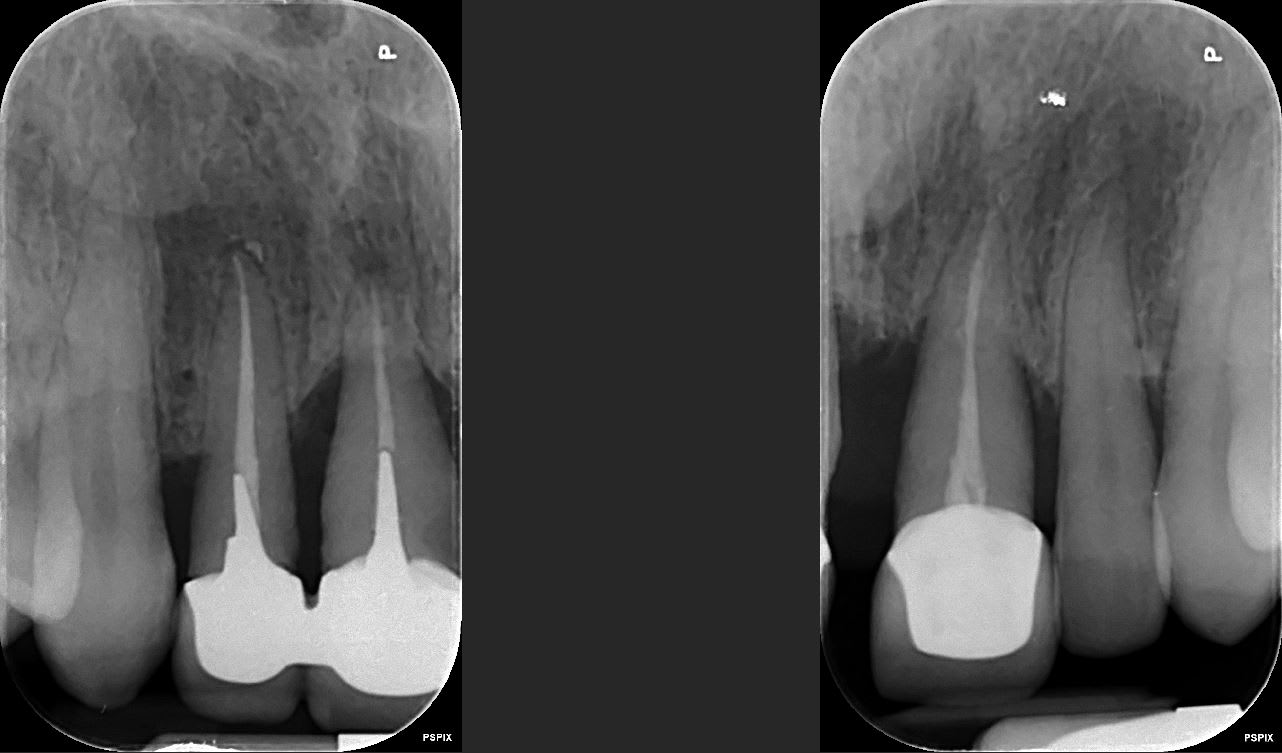

Patiente de 52 ans avec parodontite avancée

mon plan de ttt est le suivant extraction les dents aboluments non conservable (11-21-25) et tenter de garder le reste, puis réévaluer le cas apres surfacage et gingivectomie. Puis de couronner le reste: bridge 13 12 (11 21) 23, couronnes jumélées 14 15 16 17, bridge 24 (25) 26 27.

Ou extraction totale haut, implantation immédiate et mise en charge immédiate (j'adresserai a un implanto pour cela)

11 21 et 15 16 sont solidarisées ??